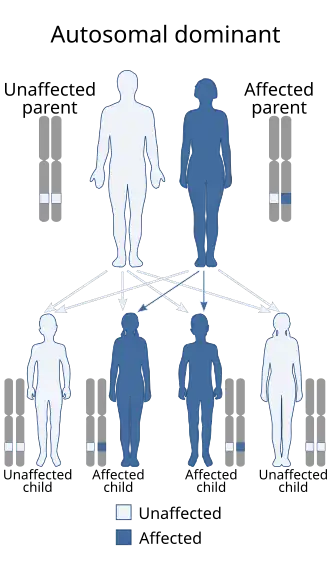

Every cell in the body has two copies of every gene (bar those found in the sex chromosomes, X and Y). In VHL disease, one copy of the VHL gene has a mutation and produces a faulty VHL protein (pVHL). However, the second copy still produces a functional protein. The condition is inherited in an autosomal dominant manner – one copy of the faulty gene is sufficient to increase the risk of developing tumours.[14][15]